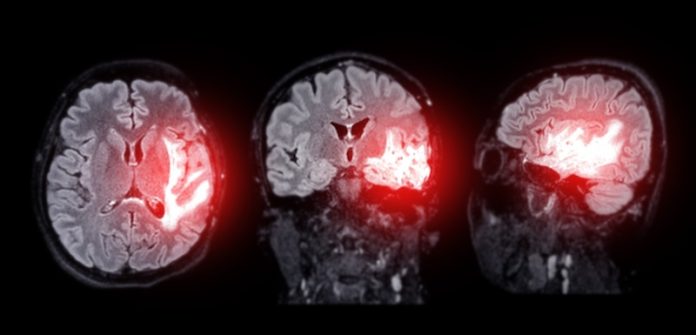

A groundbreaking study led by scientists from the Institute for Bioengineering of Catalonia (IBEC) and West China Hospital of Sichuan University has shown that a new nanotechnology-based treatment can reverse Alzheimer’s disease in mice.

Unlike traditional drug treatments, which focus on targeting brain cells directly, this approach repairs the brain’s protective shield — the blood-brain barrier (BBB).

When this barrier is damaged, it can no longer clear toxic waste efficiently, which contributes to Alzheimer’s disease. Restoring its function may help the brain heal itself.